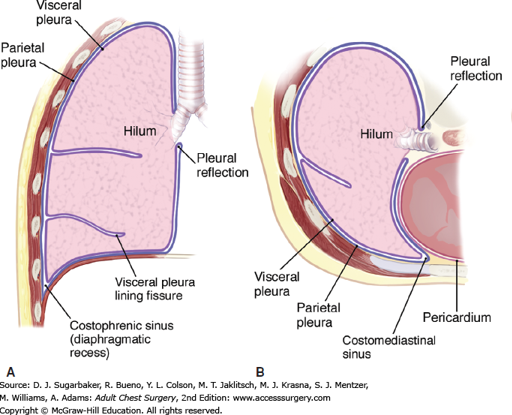

what is the:

costodiaphragmatic recess (CDR)...what is it a potential site for?

costomediastinal recess (CMR)

Potential pleural space located “between” the junction of diaphragm

and ribs

Potential site for pleural fluid accumulation

Potential pleural space located anteriorly “between” the junction of diaphragm and mediastimum

in picture you are looking from the top down...the CDR is wrapped around the 2 mickey mouse ears on the side where the ribs and diaphragm meet...the CMR is the small corners below the front circle on either side (slightly more yellow in color)

notice how the lung doesnt go all the way down and how there is a small corner where there can be an accumulation of fluid in the CDR

notice the cardiac notch in the CMR and how that can leave more space for the heart

the CDR is on the bottom of the lung in the kiddie-corner

the CMR is seen when you look down on the diaphragm from the top and see a small space in front